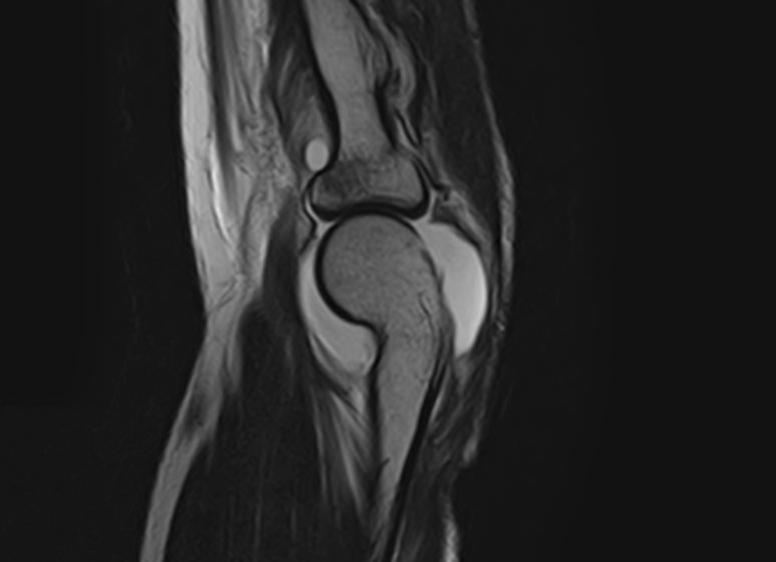

МРТ локтевого сустава: что показывает и как делают?

Магнитно-резонансная томография – это метод диагностики патологических состояний локтевого сустава, который помогает исследовать как плотную костную ткань, так и хрящи, связки, сухожилия, суставную капсулу, нервные стволы и кровеносные сосуды.

Магнитно-резонансная томография выявляет состояние всех тканей локтевого сустава

Мягкие структуры отчетливо видны на снимках, полученных с помощью МРТ, потому что этот способ диагностики основан на испускании радиоволн и их улавливании сканером после отражения от атомов водорода. Содержание водорода в мягких тканях выше, чем в костях. Метод магнитного резонанса нашел применение в исследовании структур, недоступных рентгену, который лучше определяет состояние плотных тканей.

Что показывает МРТ локтевого сустава

На снимке МРТ можно увидеть:

- Трещины костей.

- Переломы одной или двух костей локтевого сустава.

- Воспалительно-дегенеративную патологию сустава (эпикондилит наружный и внутренний). Магнитно-резонансная томография позволяет диагностировать переломы локтевого сустава

- Участки остеонекроза.

- Бурситы (воспаление суставной сумки).

- Синовит (воспалительный процесс внутренней синовиальной оболочки).

- Тендиниты (воспаление сухожилий).

- Фасциит (воспаление мышечной оболочки).

- Абсцессы (скопление гноя). Показанием к проведению МРТ является тендинит локтевого сустава

- Кисты.

- Ущемления и повреждения локтевых нервов.

- Травмы хрящей, связок и сухожилий.

- Хондроматоз, хондрокальцидоз.

- Артриты и артрозы.

- Выпот в полость капсулы локтевого сустава. МРТ назначается после перенесенной травмы сухожилий

- Гематомы.

- Липомы и другие опухоли.